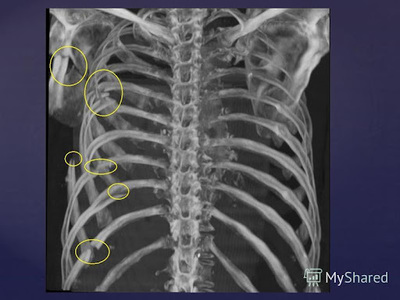

Дело было на Украине в 2002м часть называть понятно не буду, дедушки разжились бухлом, и по синему делу решили поучить жизни молодых, а так как я был из особо отличившихся, то и били меня с большим пристрастием чем остальных. В общем в одну не самую прекрасную январскую ночь, меня разбудил один из моих сослуживцев, уже прошедший экзекуцию, и я пошел в туалет, где меня уже ждали, 20 человек, бухих и скажем так, имеющие на меня зуб (это отдельная история...). Конечно прям так как на видео, лежачего не били, но... двое держат за руки спиной к стене, при этом каждый по очереди бьёт кулаком в грудь, отдельно запомнился старший сержант Сахаров - замок службы обеспечения. Я четко помню только первые два круга, третий круг уже как в тумане, помню только две мысли - молил потерять сознание, и если выживу, положу всех... Ни тому, ни другому не суждено было сбыться, хоть и не все помню, но до койки добрел сам, будить следующего не стал. Утром на зарядке пробежал 3км (перед пробежкой стянул грудь ремнями взятыми у друзей с моего призыва) брусья понятно я уже не осилил. На зарядке с нами был дежурный по части, он и инициировал телесную проверку, на которой всплыла моя грудная клетка сине-багрового цвета (мама мне в армию дала нательный крестик, оттиски от него были прямо по всей груди). Сначала меня отправили в районную, гражданскую больницу, потом ЧП разрослось аж до Генштаба, приехала проверка, полетели должности, меня отправили в окружной госпиталь, где я пролечился аж 2 дня и меня вернули обратно в часть. Дело замялось, меня лечили витаминками и йодными сеточками... Пока я отлеживался в санчасти, вся эта компания дембельнулась, и я слава богу не успел взять грех на душу (я был готов, и это чувство ненависти и бессильной ярости до сих пор со мной). Я выжил, не смотря ни на что, к переломам ребер (если правильно помню, в количестве 8-ми штук), в окружном госпитале добавили ушиб сердца, пневмоторакс и кровь в перикарде, доктор говорил, что скорее всего нужна будет операция. Служба осталась в далеком прошлом, я вспоминаю о ней даже с щемящей тоской (о плохом как-то и не вспоминается), но блядь... Отдать долг родине... Как я в свои 20 лет успел так задолжать, чтобы отдавать его такой ценой???